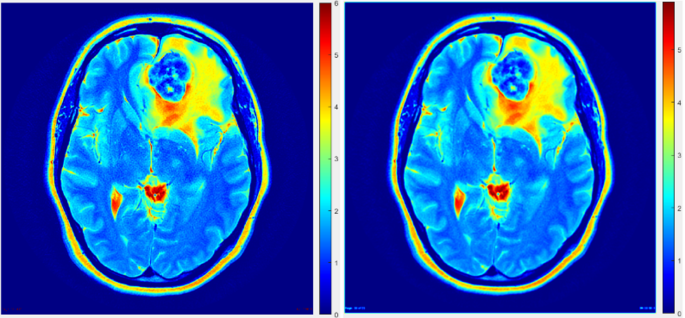

The inherent limitations of imaging systems, particularly their restricted spatial resolution, give rise to partial volume effects (PVEs) that engender spill-out phenomena in small objects or regions, as vividly depicted in Fig. 4. Consequently, when delineating ROIs for analysis, the pervasive influence of PVEs must be duly taken into account. In order to establish a reliable reference point for accurate measurements, a ground truth image was meticulously constructed by amalgamating PET images with predetermined standardized uptake values (SUVs) corresponding to distinct anatomical components, such as the tumor, regions with elevated tumor activity, skull bone, and adjacent background areas. These ground truth images serve as invaluable benchmarks, enabling precise quantification of object dimensions within the imaging domain.

Figure 4 serves as a visual illustration, juxtaposing a phantom image on the left and a conventional PET image on the right. Evidently, the PET image exemplifies a discernible attenuation of activity in diminutive entities, such as the high tumor spots region, which regrettably fails to manifest in the phantom image as prominently indicated by the absence of its characteristic red coloration. Furthermore, a notable discrepancy in spatial resolution is discernible between these two images, underscoring the criticality of addressing PVEs within imaging systems to foster enhanced precision in ROI calculations and tumor delineation endeavors.

The impact of partial volume effects (PVE) on imaging accuracy can be observed in a constructed phantom study. As shown in Fig. 4, the phantom with precise dimensions is depicted on the left, while the original PET image on the right demonstrates blurred object boundaries and a loss of activity in small objects (indicated by the white arrow) due to PVE. This highlights the need for advanced imaging techniques to mitigate PVE and improve resolution and activity quantification in PET imaging.